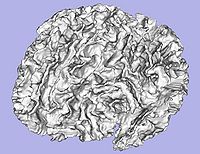

- 1.7. Genus zero cortical surface creation and inflation

- 1.7.1. Genus zero cortical image and surface creation

- Tool: GenusZeroImageFilter (UNC Slicer3 external module)